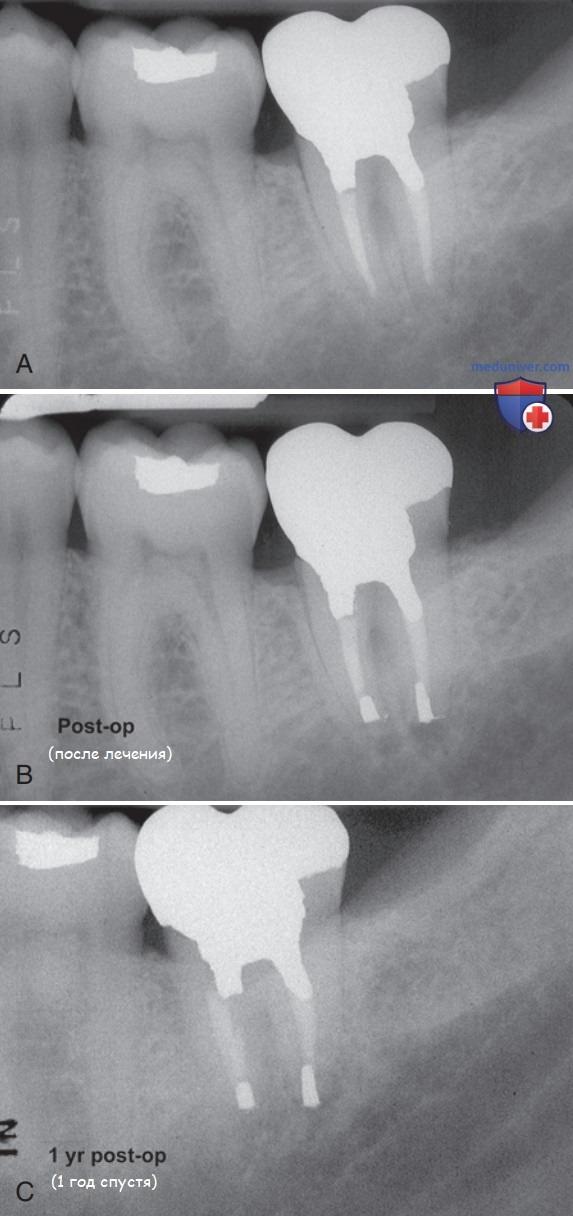

Реплантация зуба: Этапы и особенности операции